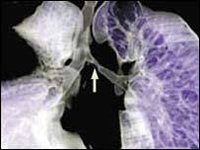

血行播散型肺結核急性粟粒型結核是急性全身血行播散型結核病的一部分,起病急,有全身毒血症狀,常伴髮結核性腦膜炎,X線顯示雙肺在濃密的網狀陰影上,滿布境界清晰的粟粒狀陰影,直徑約2mm,大小及密度大體相等。病初胸片可能無明顯粟粒狀影,或僅僅有關瀰漫性網狀改變易誤診為傷寒、敗血症等其他發熱性疾病。若人體抵抗力較強,少量結核菌分批經血液循環進入肺部,其血行播散灶常大小不均勻、新舊不等,在雙肺上中部分部呈對稱性分布,稱為亞急性過慢性血行播散型肺結核。其病情發展緩慢,通常無顯著中毒症狀,患者可無自覺症狀,偶於X線檢查時才被發現。此時病灶較穩定或已硬結癒合。

4.x 線胸片兩肺見典型粟粒陰影 。胸CT急性血行播散型肺結核表現為直徑1-3mm大小、密度及分布均勻的粟粒結節;而亞急性和慢性患者表現以上中肺野為主的3-7mm大小、密度及分布不均勻的結節。結節的邊界多數尚清晰,但也有表現邊界模糊;結節隨機分布於肺小葉、小葉間隔及胸膜下。